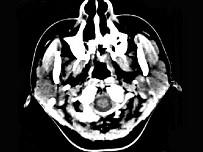

问题 女,28岁,左耳前肿块34月余,PE:左侧耳前可触及肿块,境界尚清、质硬、活动度尚可,CT如图所示,最可能诊断为()

选项 A.神经纤维瘤 B.腮腺恶性混合瘤 C.腮腺腺淋巴瘤 D.副神经节瘤 E.腮腺混合瘤

答案 E